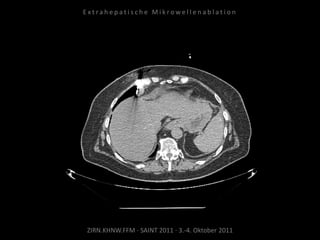

Patient: Männlich, 74 Jahre

Diagnose: Malignes Melanom,

Metastasierung lokal begrenzt

(3 peritoneale Metastasen).

Ausgangsbildgebung:

CT vom 21.12.2009